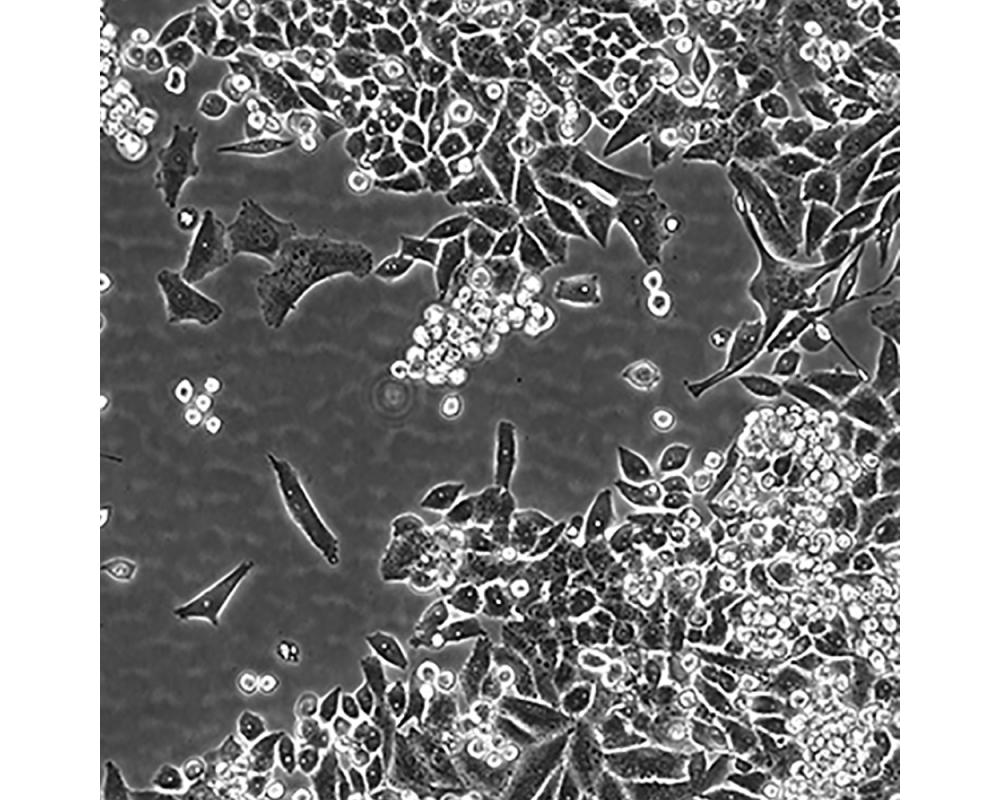

MiaPaCa-2

中文名稱 人胰腺癌細胞

組織來源 胰腺導管癌;男性

生長特性 貼壁

培養基 1640,90%;FBS,10%;雙抗。

培養條件 Atmosphere: Air, 95%; CO2, 5%。Temperature: 37℃